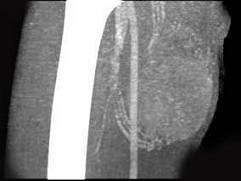

问题 男,30岁,主诉右大腿肿块年余,逐渐增大,局部胀痛及压痛,请根据图像表现,选出最佳选项 ( )

选项 A、横纹肌肉瘤 B、神经纤维瘤 C、血管瘤 D、脂肪瘤 E、脓肿

答案 A